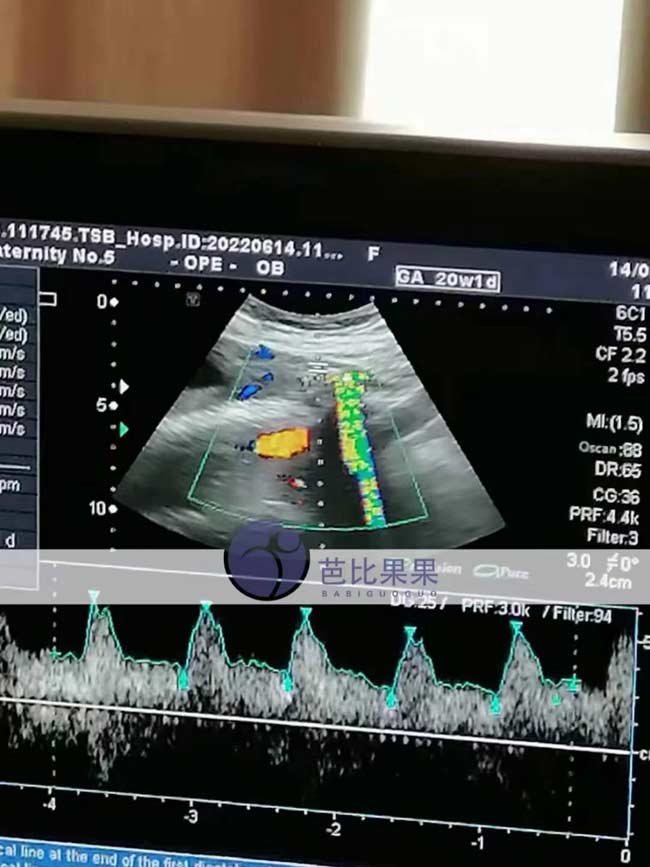

z女士已经孕16周多的乌克兰试管妈妈去医院照B超

z女士乌克兰试管妈妈去医院照B超,已经孕16周多了,胎宝宝很健康。这个时期的宝宝发育的很快,通过B超看到宝宝的头部、骨骼、腹腔脏器正健康发育着。